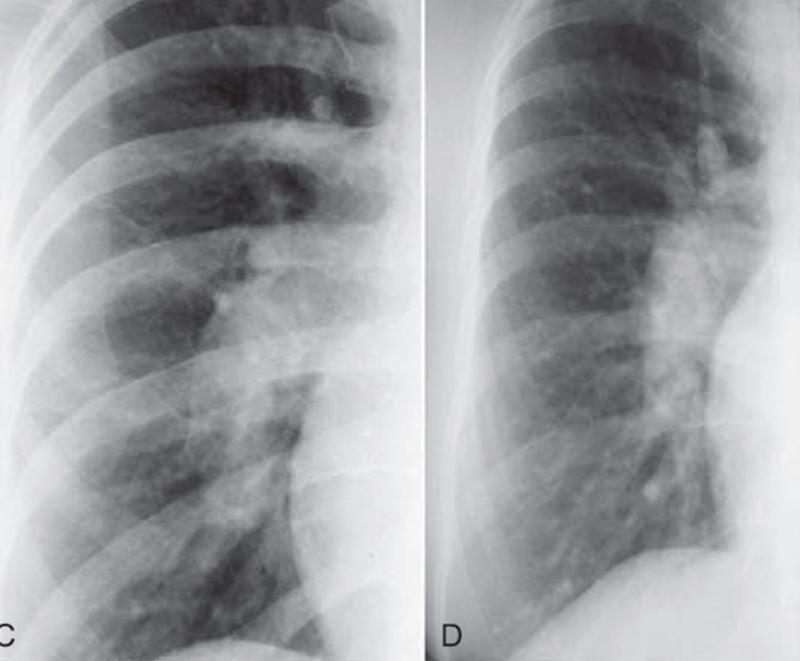

UNDERSTANDING LUNG NODULES

UNDERSTANDING LUNG NODULES pulmonary nodules (SPN). Lung nodules are very common – at least 50% of people have them by the time they are 50 years old. The challenge is figuring out which nodules are or will become cancer. ... Read Full Source